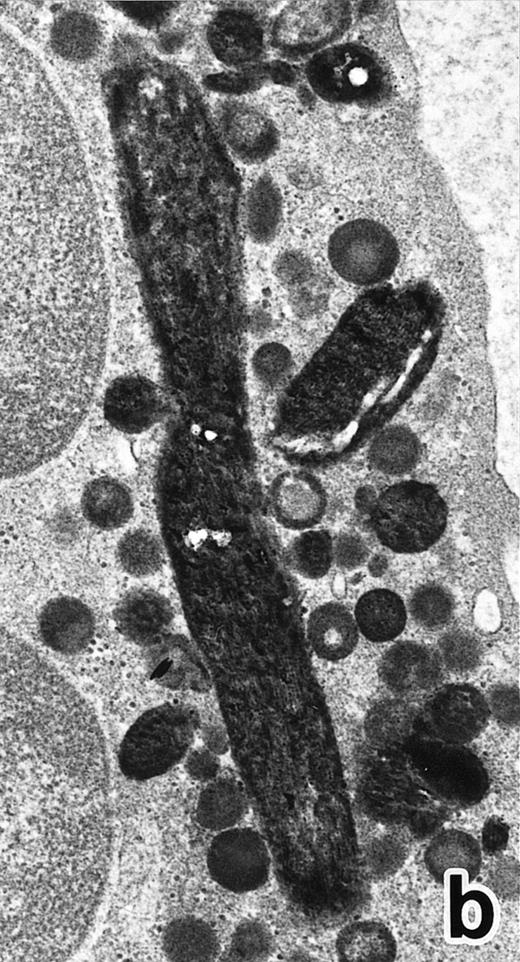

(a) A PMN in patient no. 2 after 10 days of ATRA treatment. The nuclei are irregularly lobulated, with some of them being connected by nuclear filamentous structures, and heterochromatin is condensed along the nuclear membrane. (Original magnification × 13,100.) (b) Higher magnification of a portion of the cell in (a). The cytoplasmic granules are large and spherical, and some of them contain flocculent material and central cores with higher electron density. (Original magnification × 20,200.)